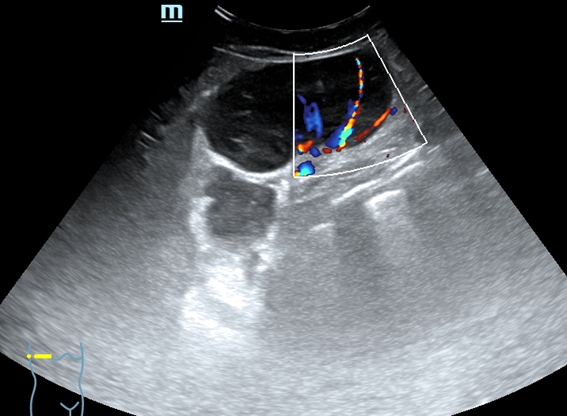

Eco clínica axilar dcha: se visualizan 3 nódulos contiguos de 4,7 x 3,39 cm y 5,4 x 2,9 cm y 5,3 x 3,9 cm. Los 3 con contornos definidos, hipoecoicos, contenido homogéneo, con refuerzo posterior, hipervascularizados,

Ante la sospecha de conglomerados de adenopatías de características tumorales se exploran ecográficamente otras zonas ganglionares visualizándose adenopatías con características tumorales (aumentadas de tamaño, redondeadas, hipoecoicas homogéneas con borramiento de hilio y vascularización cortical) en cuello, axila izquierda y región inguinal izquierda.